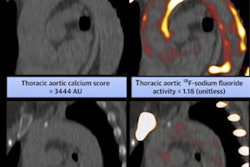

A 40-year-old patient with clinically active r-AxSpA and extensive bone edema on F-18 NaF-PET/MRI at baseline and at four-month follow-up. Image courtesy of Dr. Nils-Martin Bruckmann.Three independent readers evaluated all images for inflammation (bone marrow edema) and structural lesions. F-18 NaF uptake was recorded on the level of sacroiliac joint quadrants and vertebral quadrants. The researchers analyzed a total of 128 sacroiliac joint quadrants and 920 vertebral quadrants at each time point.